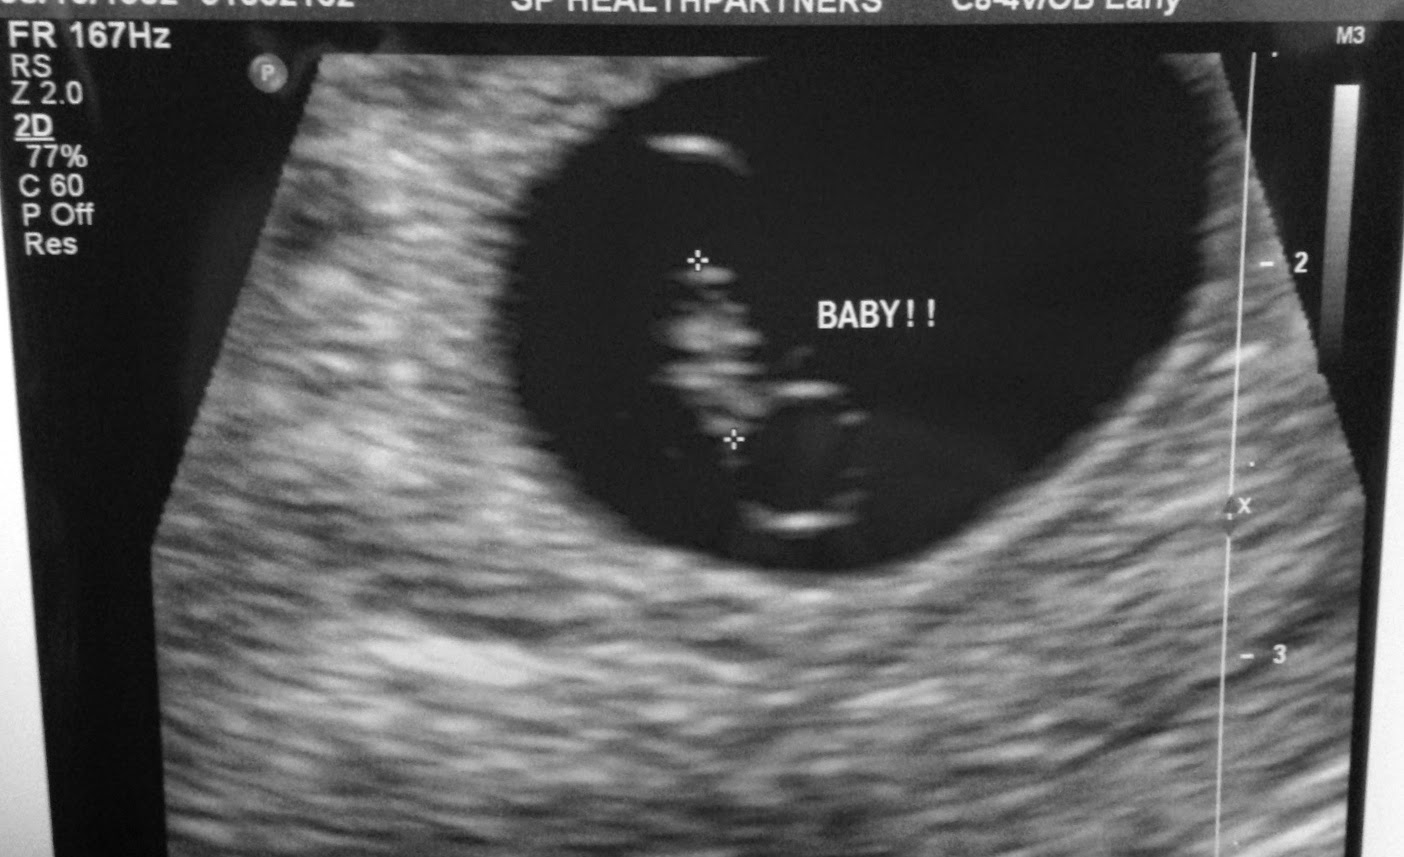

When I went in for an early ultrasound at eight weeks pregnant, I expected one of two things: I'd either see a healthy, thriving baby, or that I'd be offered condolences; that they were sorry to be the bearers of bad news, but there's just no heartbeat to be found; that my baby had passed. I'm not entirely sure which outcome I was expecting, realistically, since I'd been spotting intermittently throughout the duration of my pregnancy, and I knew that even though I wasn't particularly losing sleep over it, that miscarriage would be a distinct possibility. Because at the same time, I knew beyond a shadow of a doubt that this pregnancy was real. I felt it. I experienced all those familiar symptoms I had the first time around - the excessive fatigue and hunger, the mood swings, and those little uterine twinges that reminded me that a tiny human was coming into being within my body.

While lying on the table, though, with that cold goop on my abdomen and the ultrasound wand moving slowly across my lower belly, something in the back of my mind - or my heart - raised a red flag. There was my baby - albeit smaller than I expected it to be - but with a beating heart that just didn't seem quite up to par. The ultrasound technician didn't say anything, but when she timed the heartbeat, I knew something was wrong. She eventually stepped out, to go get the doctor on staff to come in for a consultation; and I waited in that dimly lit room for just long enough to know that their hushed discussion out in the hallway was probably focused more on how they were going to tell me than it was on what they were going to have to say.

I can only recount little blips of what the doctor told me - I think most of what he said washed away as his voice filled up the room and my ears, and eventually started to sound like white noise. "The baby is far too small for how far along you are - and its heart rate is very slow. You have a first OB appointment scheduled directly after this, I know," he said, "...but I'm going to recommend that you not bother going. We'll schedule another ultrasound a week from now, and if we don't see substantial progress, we'll know for certain that this baby isn't developing properly and we'll take matters from there." "I'm sorry this isn't good news," he continued, and asked if I had any questions. "No? Okay. We'll see you next week." Questions? I had a million of them. I had zero. I had a ringing and a buzzing filling my head and I needed to run away. I was thinking everything and nothing and everything and nothing. I was numb and I was exploding.

And when the day came, and I laid down on the table for that follow-up ultrasound, and saw my tiny, lifeless baby on that screen, it was like something in me finally felt free to exhale. Like the torture I'd been feeling all week prior wasn't so much associated with the impending loss as it was with the utter uncertainty that existed surrounding the whole thing. I had grieved, I had celebrated, I had prayed, I had begged, and I had hoped - and then finally, at long last, I was able to breathe. A little shallower, albeit, and through tears, but it surprised me that I ended up feeling more relief than anything else. At last I knew.